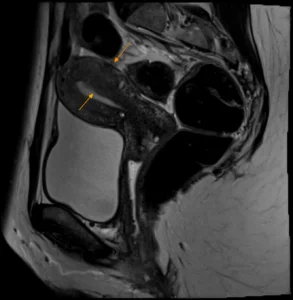

Normaler Uterus (rechts), Uterus mit Adenomyose (links) | |||